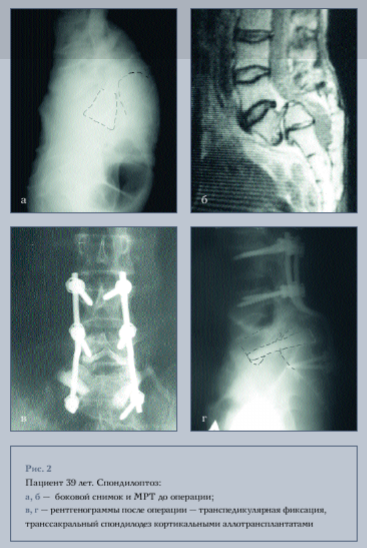

В зависимости от уровня фиксации мы разделили больных на 4 группы: больным I группы произведена фиксация двух сегментов, винты вводились в L4, L5 и S1 позвонки (рис. 1); в остальных группах производилась фиксация трех сегментов, при этом во II группе винты вводились в L3, L4, L5 и S1 позвонки, в III - в L3, L5 и S1 позвонки и в IV группе в L3, L4 и S1 позвонки (рис. 2).

меньшей степени устранялись угловые смещения, такие, как сагиттальная ротация и наклон позвонка, так как смещаемый кзади позвонок двигался по наименьшему радиусу благодаря наклону винта относительно головки и, следовательно, стержня. В I группе (фиксация L4—L5—S1), где мультиаксиальные винты использовались в гораздо меньшем соотношении, величина коррекции угла сагиттальной ротации была больше. В свою очередь наименьшее вправление и снижение угла Митбрейта после операции было получено у пациентов IV группы, которым не вводили винты в смещенный позвонок, при этом не происходило прямого редукционного воздействия, а редукция достигалась лишь за счет дистракции. О трудностях введения винтов в смещенный позвонок L5 в связи с анатомическими особенностями, выраженным смещением и предшествующими операциями на данном уровне сообщается в литературе [12], при этом авторы дополнительно выполняли транссакральный спондилодез. Мы также в двух случаях в данной группе произвели транссакральный спондилодез L^-Sy При этом необходимо отметить, что при введении сзади в позвонок L5 аллотрансплантатов последние приподнимали тело смещенного позвонка (рис. 2), что отражалось в улучшении таких параметров, как угол сагиттальной ротации и межзвенный угол S1.